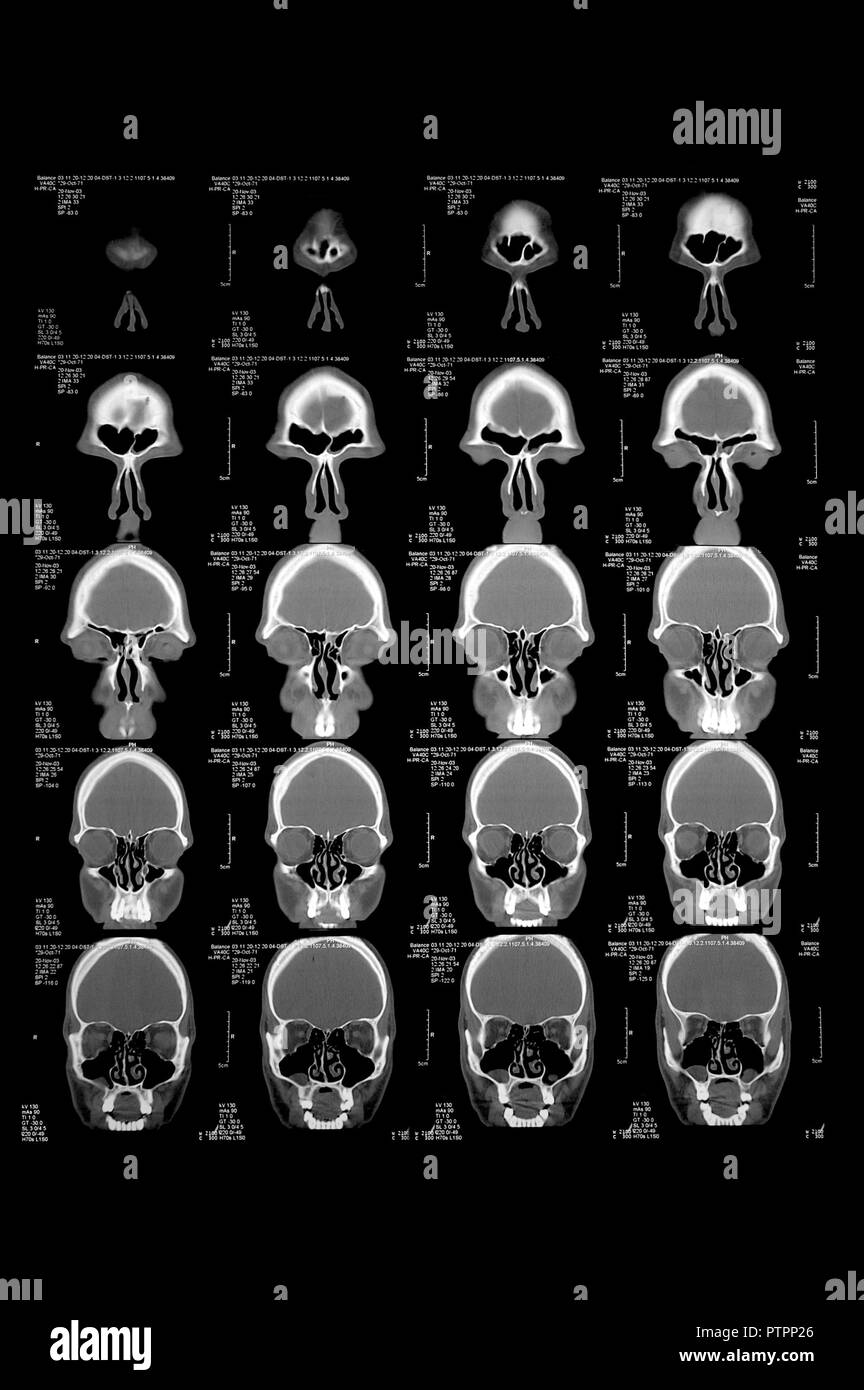

Tête dans la tomographie assistée par ordinateur, l'image CT Banque D'Imageshttps://www.alamyimages.fr/image-license-details/?v=1https://www.alamyimages.fr/tete-dans-la-tomographie-assistee-par-ordinateur-l-image-ct-image221776414.html

Tête dans la tomographie assistée par ordinateur, l'image CT Banque D'Imageshttps://www.alamyimages.fr/image-license-details/?v=1https://www.alamyimages.fr/tete-dans-la-tomographie-assistee-par-ordinateur-l-image-ct-image221776414.htmlRFPTPP26–Tête dans la tomographie assistée par ordinateur, l'image CT